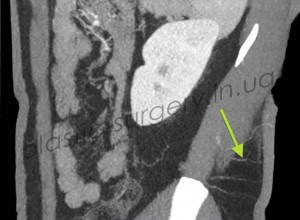

После предварительной локации точки выхода сосудов в покровные ткани в области поясницы, рядом с раневым дефектом с помощью аудио-допплера, больному было проведено более детальное обследование – КТ с ангиографией. При проведении исследования была визуализирована одна из люмбальных артерий и её перфорант справа от позвоночника, уточнено место выхода перфоранта, направление его оси и ветвление в покровных тканях (Рис. 3, 4, 5).

Рис. 4. Снимок компьютерной томографии с ангиографией, стрелкой отмечена люмбальная артерия и её перфоранты, выходящие в покровные ткани. (справа).